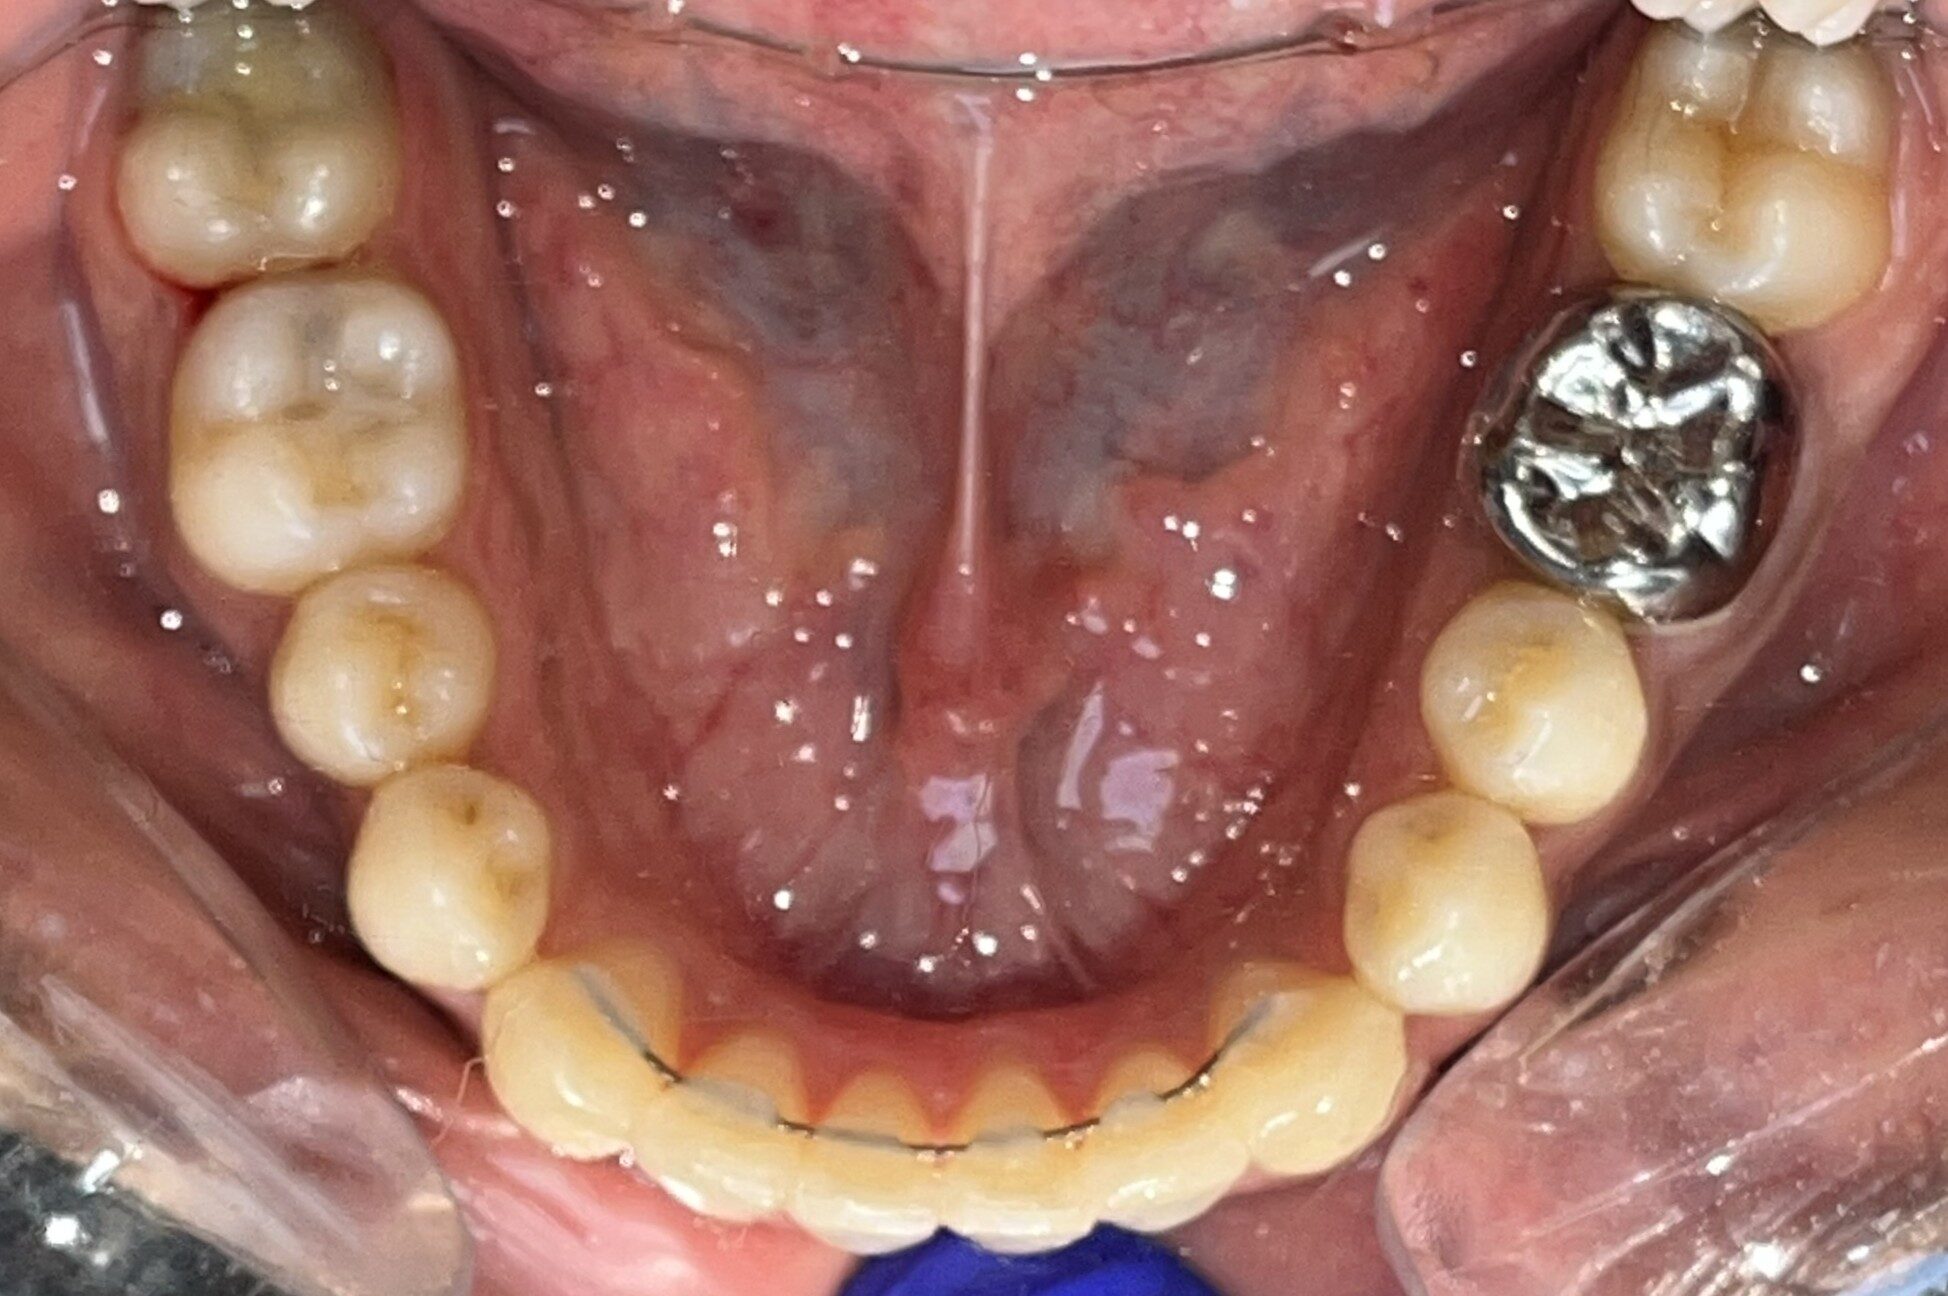

Before: Lower

During The Treatment